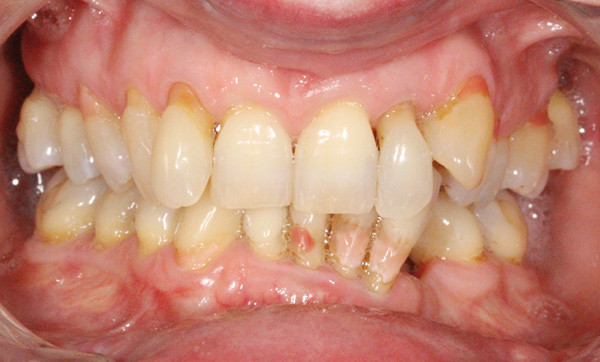

Sur le plan dentaire (fig. 4 à 8), elle présente une classe II subdivision gauche, un surplomb diminué et un recouvrement très augmenté. La formule dentaire est incomplète. Les incisives maxillaires et mandibulaires sont très linguoversées. Le milieu mandibulaire est dévié de 5 mm à gauche. À noter également, une DDM importante (en tenant compte du remplacement prothétique de 33 et 34).

Sur le plan parodontal, la patiente présente une parodontite chronique stabilisée généralisée modérée à sévère (fig. 9).